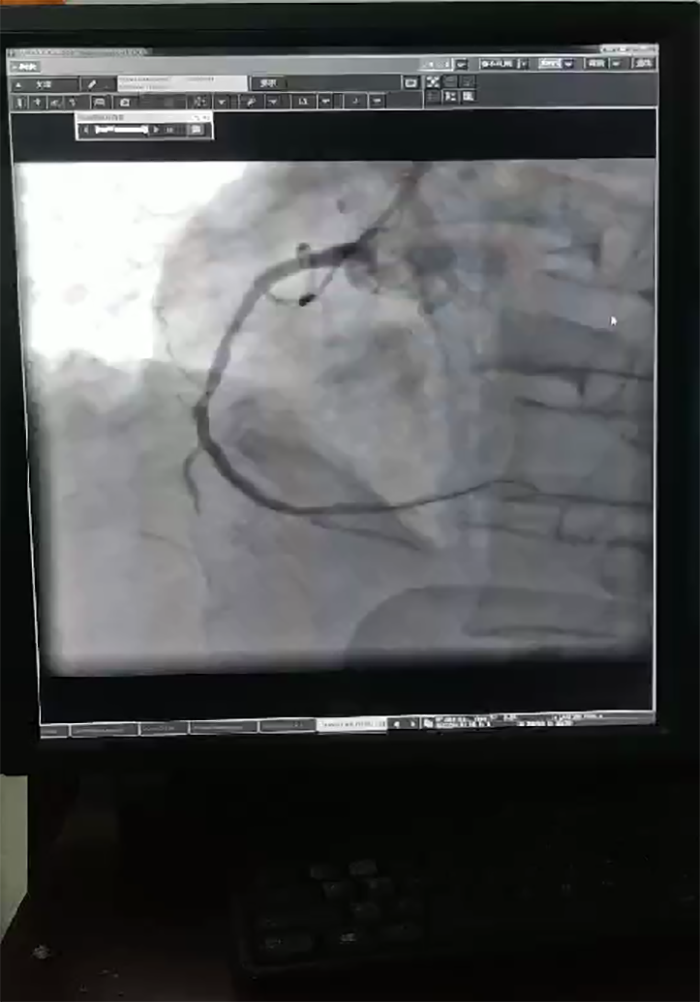

不久前,市民张先生突发胸痛后心脏骤停,120接到患者以后立即为患者行心电图检查,并将患者检查结果传到胸痛中心会诊微信群里。心血管内科副主任医师蔡亚滨远程通过心电图立即评估患者病情,判断患者很可能是急性心肌梗死,急需做介入手术。途中急救人员一边密切监护病情,一边给患者服用急诊一包药、建立静脉通道等必要处理,一切都在紧张有序中进行。 医院胸痛中心绿色通道同时启动,导管室、介入手术团队等做好一切术前准备,争取救治时间。经过复查心电图,急查肌钙蛋白,结果表明患者很可能是急性大面积心肌梗死合并心源性休克,心内科介入团队随即马上又进行了IABP保护下选择性冠脉造影术。

“在冠状动脉造影术下,显示患者心脏左主干加上三支血管病变,这种情况基本属于九死一生。”跳蛋视频 心血管内科主任蔡亚滨介绍,多学科联合抢救团队马上确定救治方案,ICU团队先上V-A ECMO(体外膜肺氧合技术,起到一个人工心肺的作用)稳定患者状况,随后心血管内科介入团队在ECMO保护下进行介入手术(PCI),在患者左主干前降支、回旋支、右冠植入支架,90分钟后顺利完成手术。术后第4天,患者心率、血压稳定,顺利拔除ECMO动静脉导管,术后第10天转入普通病房继续诊治。